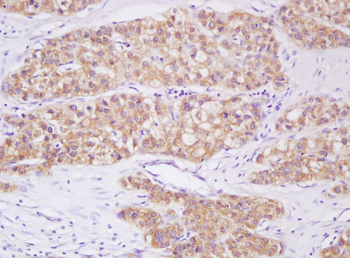

Phospho-Smad3 (Ser423 + Ser425) Rabbit Polyclonal Antibody [orb6983]

FC, IF, IHC-Fr, IHC-P, WB

Bovine, Canine, Equine, Gallus

Human, Mouse, Porcine, Rat

Rabbit

Polyclonal

Unconjugated

100 μl, 200 μl, 50 μlPhospho-SMAD5 (Ser463 + Ser465) Recombinant Rabbit Monoclonal Antibody [orb559123]